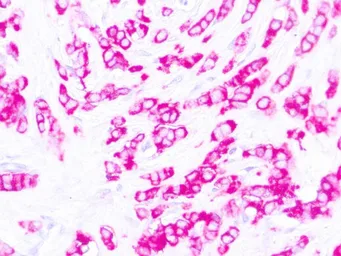

Anti-MUC1 antibody [E29] (ready-to-use) used in IHC (Paraffin sections) (IHC-P). GTX05135

GTX05135 IHC-P Image

IHC-P analysis of human breast carcinoma tissue using GTX05135 Epithelial Membrane Antigen antibody [E29] (ready-to-use).